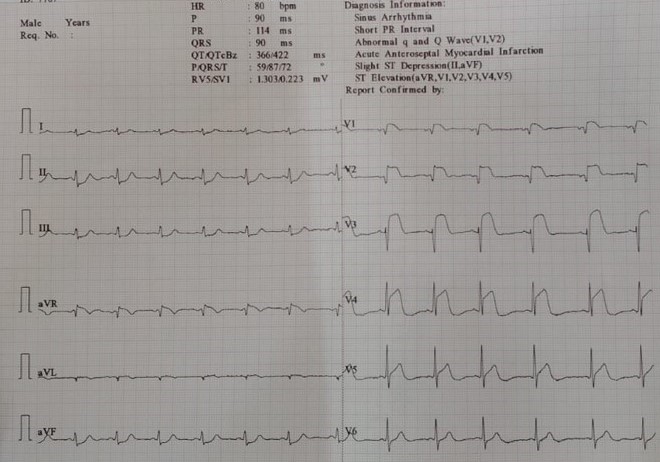

• A 65 Year old male with Kyphoscoliosis and B/L LL polio(Fig 1) presented to ER with chest pain, he was diagnosed as ACS-AWMI lysed outside. On evaluation his HR was 100 bpm, BP 90 Systolic. On examination his chest was clear and normal heart sounds heard. ECG revealed Sinus tachycardia @ 105 bpm and ST elevations in V2-V4(Fig2). 2D ECHO revealed EF of 38% with RWMA in LAD territory. In view of failed lysis, we shifted him to Cathlab for Rescue PCI.